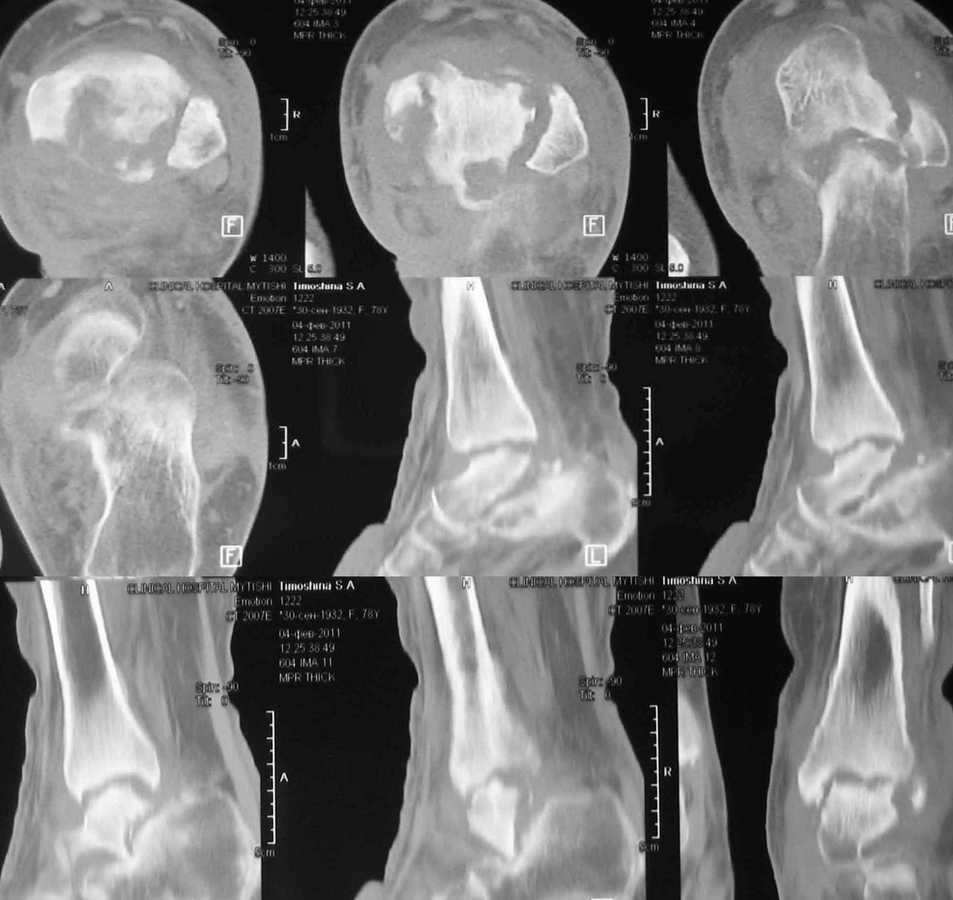

Женщина 78 лет. После инъекции дипроспана (несколько месяцев назад) развился артрит с некрозом тарана

Женщина 78 лет. Полгода назад в сустав дважды вводили дипроспан с целью лечения артроза. Спустя некоторое время появился отек, боль и пр. Три месяца назад дугообразным разрезом вскрыли абсцесс по задне-внутренней поверхности голеностпоного сустава. Теперь там свищ со скудным гнойным отделяемым.

КТ и внешний вид на картинках.